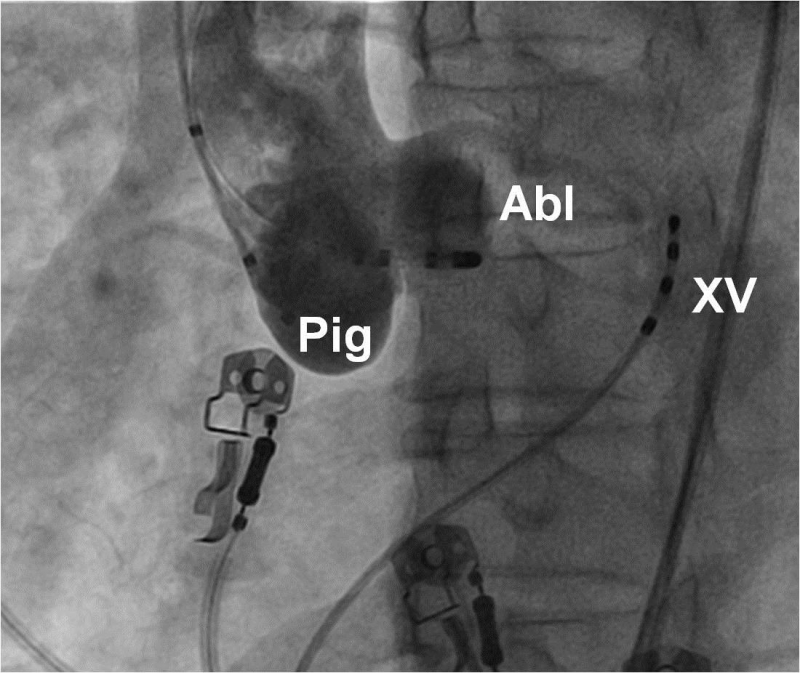

Phần lớn có nguồn gốc từ đường ra thất phải hoặc ở vách liên thất bên trái, thường xảy ra trên những người không có bệnh lý tim mạch thực tổn. Cơn tim nhanh thất có nguồn gốc từ đường ra thất phải biểu hiện trên điện tâm đồ với QRS có dạng blốc nhánh trái và trục điện tim quay xuống dưới, cơn tim nhanh thất có nguồn gốc từ mặt trái vách liên thất có điện tâm đồ với dạng blốc nhánh phải và trục điện tim hướng lên trên. Ngoài ra, tim nhanh thất/ ngoại tâm thu thất vô căn còn có thể khởi phát từ những vị trí khác như xoang Valsalva, trên van động mạch phổi, vòng van ba lá, vị trí cạnh bó His, vòng van hai lá…

Triệt đốt các cơn tim nhanh thất được thực hiện bằng cách đưa ống thông đốt vào trong các buồng thất qua đường tĩnh mạch hoặc động mạch đùi hoặc qua đường xuyên vách liên nhĩ. Ổ ngoại vị được xác định bằng vị trí ghi được điện thế hoạt hoá nội mạc sớm nhất (earliest activation mapping) hoặc bằng phương pháp tạo nhịp (pace mapping).

Hình 16: Vị trí các ống thông trên hình ảnh X quang trong triệt đốt ngoại tâm thu thất khởi phát từ xoang Valsalva trên góc nghiêng trái 30 độ: XV: điện cực xoang vành, Pig: ống thông Pigtail chụp xoang Valsalva, Abl: điện cực triệt đốt được đưa vào trong lòng xoang Valsalva lá vành trái, phía trên khoảng 1 cm là lỗ xuất phát của thân chung động mạch vành trái.